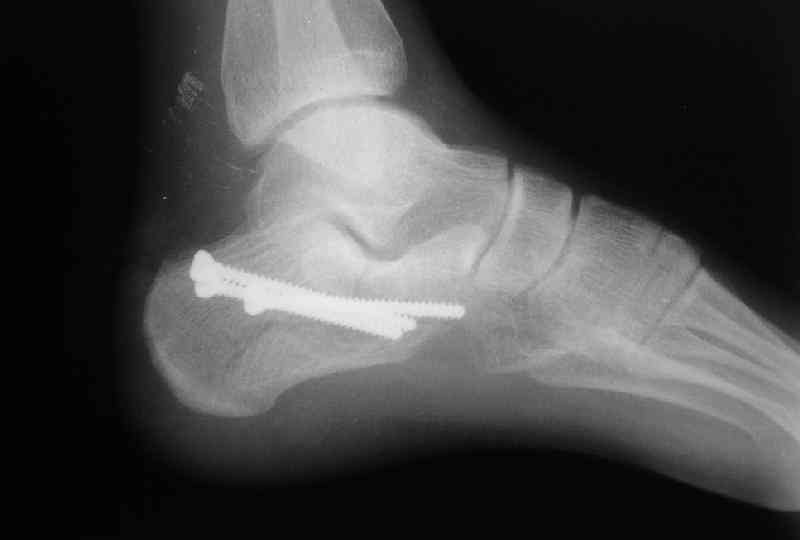

Вправление задней фасеты с восстановлением таранно-пяточного угла возможно минимально-инвазивным методом Essex-Lopresti - под ЭОП или графическим контролем введенной в пяточный бугор толстой спицей или стрежнем Штеймана, которые служат рычагом. Для удержания вводим несколько тонких спиц Киршнера, фиксация в эквинусе.Подробнее в Margo anterior 1-2 2000\издание АО Матис в России, на сайте www.mathys.ru в архиве есть все выпуски. Метод внедрен у нас с 2000 года и дает неплохие результаты.

Действительно архив Margo Anterior начинается с 2001 года.Но я могу эту статью по лечению переломов пяточной кости,очень обстоятельную, санировать и выслать мылом на ваш адрес или разместить на rapidshare ru и указать ссылку на форуме. несколько тонких спиц вводятся в разных направляениях при многофрагментарных переломах иногда через подтаранный сустав для удержания репозиции. Их и стержень удалем через 6 недель.